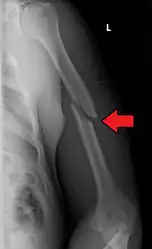

A transverse fracture of the humerus shaft -